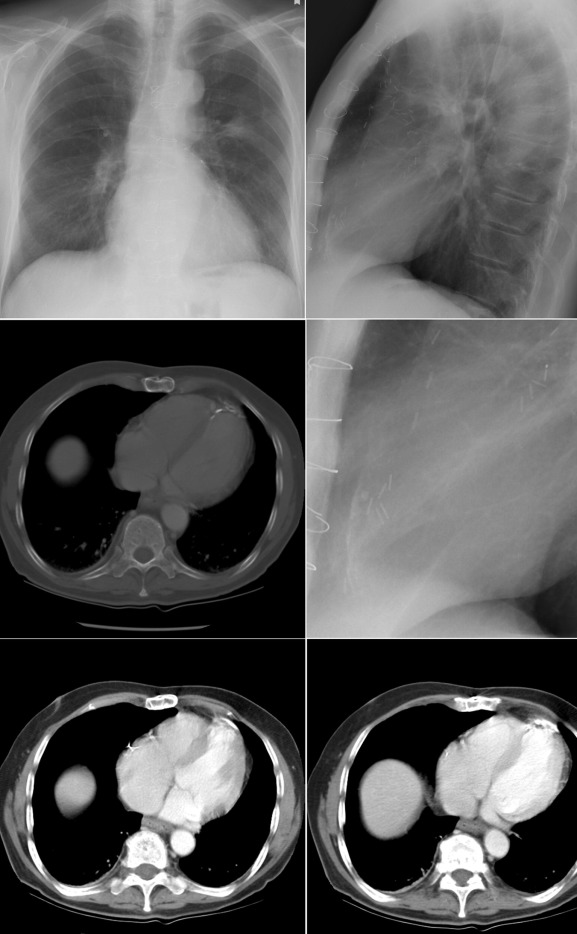

Pericardial calcification ( Figs. 27-1 to 27-4 ) is most prominent in the interventricular and atrioventricular grooves, and lateral to the right atrial and ventricular walls ( Graphic 27-1 ). When looking for pericardial calcification, it is necessary to scrutinize the lateral chest radiograph well, particularly the diaphragmatic surface. Pericardial calcification does not usually involve the left heart as much the right heart, and it does not often involve the apex (which, if calcified, is far more often due to prior infarction). Pericardial calcification should prompt serious consideration of the diagnosis of constrictive pericarditis, and clinicians should seek other radiographic and clinical features of constriction.

Myocardial Calcification ( Figs. 27-5 to 27-9 )

A calcified ventricular aneurysm is seen as a fine dense line when viewed on edge and is consistent with an old transmural infarction. On the frontal chest radiograph, an anterolateral, or apical, calcified aneurysm may be visible. Rarely, a calcified septal aneurysm may be seen on a lateral chest radiograph. Myocardium may calcify following traumatic injury as well as postinfarction.